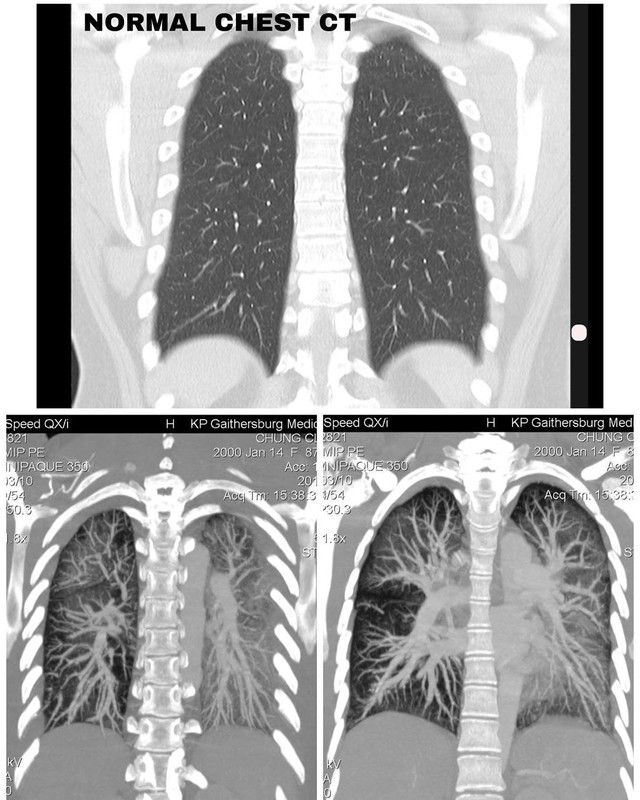

Claire lalu diperintahkan untuk melakukan CT scan pada paru-parunya, dan ternyata hasilnya sangat mengejutkan.

Hasil CT Scan menunjukkan paru-paru Claire berwarna hitam.

Potret hasil CT scan paru-paru Claire Chung

Potret hasil CT scan paru-paru Claire Chung (Instagram/clairechunggg)

"Paru-paru saya yang berusia 19 tahun benar-benar berkabut dan putih di pemindaian, seluruhnya menutupi kedua paru-paru," ujarnya dalam keterangannya.